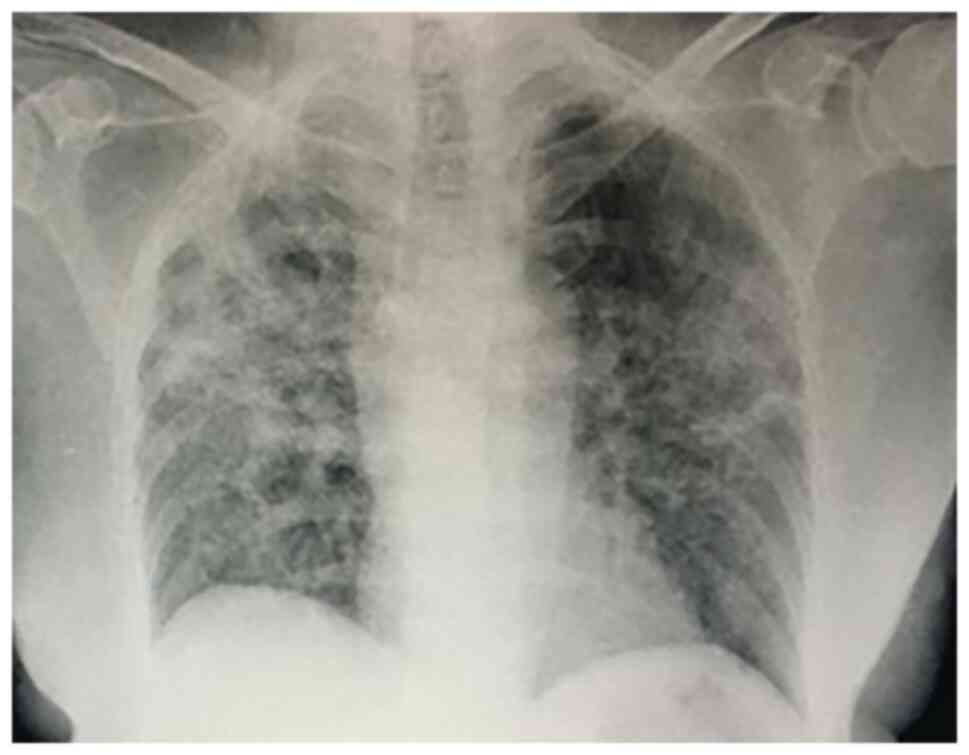

A 73-year-old woman was admitted in May 2021 to the Department of Infectious Disease in the Clinical Infectious Diseases Hospital with a cough, shortness of breath and fatigue that was found to be due to severe SARS-CoV-2 pneumonia by nasopharyngeal swab. The patient had multiple cardiovascular risk factors, including arterial hypertension, type 2 diabetes mellitus, obesity (36.7 BMI) and a history of coronary heart disease for a number of years. Chest X-rays showed bilateral pneumonia with peripheral consolidations and a reticular pattern due to septal thickening with ground-glass opacities (Fig. 1). From admission, the patient exhibited dyspnea, with acute respiratory failure (mixed venous oxygen saturation, 78%), and blood tests showed inflammatory syndrome [elevated erythrocyte sedimentation rate (80 mm/h; cut-off, 3-9 mm/h), and fibrinogen (820 mg/dl; cut-off, 196-372 mg/dl), C reactive protein (120 mg/l; cut-off, 0-5 mg/dl), ferritin (1,206 ng/ml; cut-off, 70-435 ng/ml) and IL-6 (276 pg/ml; cut-off, 0-7 pg/ml) levels]. The serum level of procalcitonin was normal. The patient received corticosteroid therapy (8 mg dexamethasone twice daily) from admission, as well as tocilizumab (2x800 mg twice daily), remdesivir (200 mg on day 1, then 100 mg daily for 5 days) and prophylactic low molecular weight heparin (4,000 IU enoxaparin daily). The clinical and biological evolution was favorable during the first hospitalization period, but on the 14th day, the patient developed a fever (38.5˚C temperature) and their general condition worsened. Laboratory tests revealed a high procalcitonin level of 4.1 ng/ml (cut-off <0.5 ng/ml), mildly elevated liver transaminase levels (ALT, 120 u/l; cut-off, 4-36 U/l; AST, 163 U/l; cut-off, 5-40 U/l) and a decreased estimated glomerular filtration rate (41 ml/min/1.73 m2). The hs-troponin (152 ng/l; cut-off, 4.9-50 ng/l) and D-Dimer (1.78 µg FEU/ml; cut-off, 0-0.5 µg FEU/ml) levels were also elevated. The patient developed respiratory distress (arterial oxygen partial pressure/fractional inspired oxygen ratio <100) that required non-invasive continuous positive airway pressure ventilation. A pulmonary computed tomography scan was therefore performed, which ruled out a pulmonary embolism and showed diffuse ground-glass opacities, peripheral consolidation and bronchiectasis (Fig. 2). Blood cultures were positive for Enterococcus faecium sensible to vancomycin, linezolid, teicoplanin and tigecycline.

Figure 1

Chest X-ray image showing bilateral pneumonia with peripheral consolidations and a reticular pattern due to septal thickening, with ground-glass opacities.